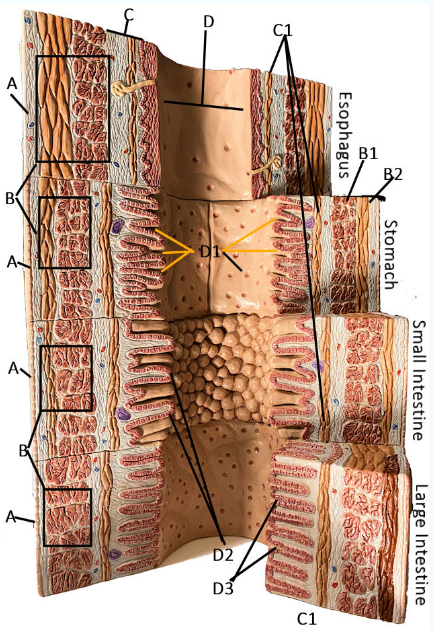

GI Cytology

A

Serosa

B Esophagus

Muscularis externa: skeletal, skeletal/smooth, and smooth, circular and longitudinal

B Stomach

Oblique, circular, and longitudinal smooth muscle

B Small intestine

circular and longitudinal smooth muscle

B large intestine

circular and longitudinal smooth muscle

C

Submucosa: areolar and dense connective tissue

D

Lumen

D1

Gastric glands/pits

D2

Villi of small intestine

D3

Intestinal crypts of large intestine